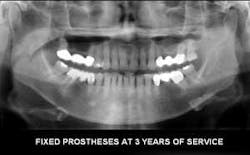

1. Panoramic radiographs. Panoramic radiographs are especially helpful for patient education, because the patient can easily orient the images to their own mouth. Digital panoramic radiographs are much better than analog panoramic radiographs for patient education. You can modify them in many ways (adding contrast, cropping, magnifying) to simplify the patient educational value.

3. Digital radiography. I strongly suggest incorporating digital radiography into your practice as soon as you can afford it (Figures 2 to 5). Although the initial digital images are not better than analog images, they can be enlarged, colored, textured, and have contrast changed, thereby increasing patient education potential and your diagnostic ability.